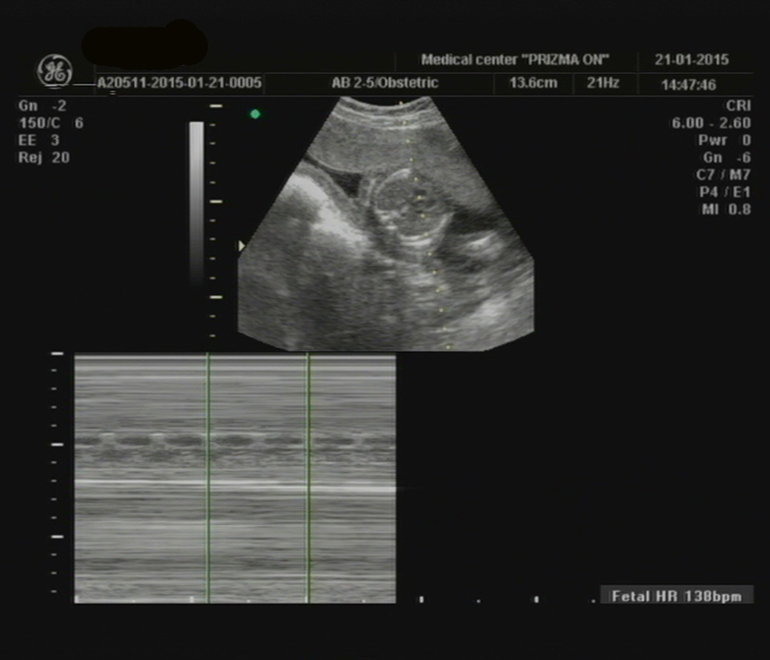

Сдали мы кровь, на второй скрининг, всё у нас хорошо. Сделали УЗИ, ровно в 20 недель, всё у нас в норме. Теперь малыш отстаёт на 3 дня, от для М и поставили нам 19 недель 5 дней, но в заключении указали 20 ровно недель... Сказали что мальчик, но нашли только мошонку. Теперь жду следующего УЗИ 24й неделе, схожу в другое место, может там нам малыш всё таки решит показать кто он, а то всё время ножки зажимает...

Вот такое чудо у нас в пузе